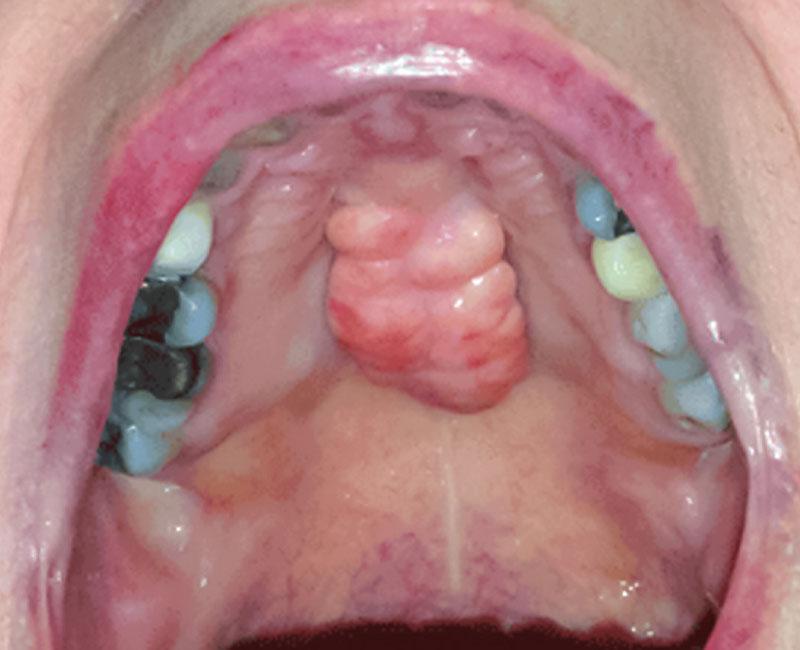

A torus palatinus almost always forms in the center of your hard palate (the roof of your mouth). You might be born with it, or it might develop gradually over time.

- One or more bony growths (bumps) in the center of your hard palate.